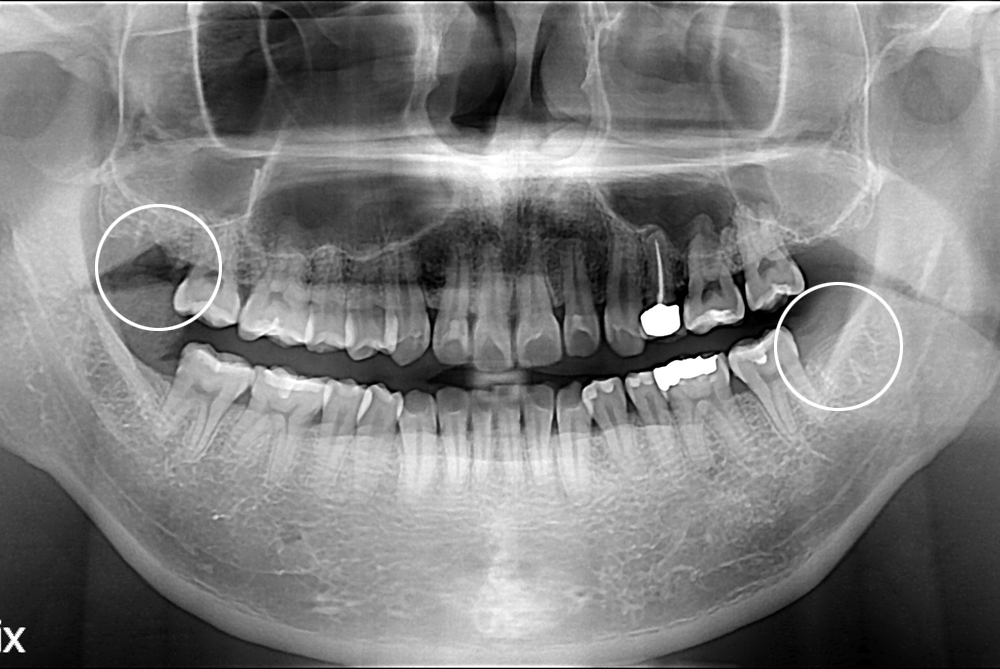

[사랑니] 난발치 사랑니 발치

치료후 : 2017-03-10